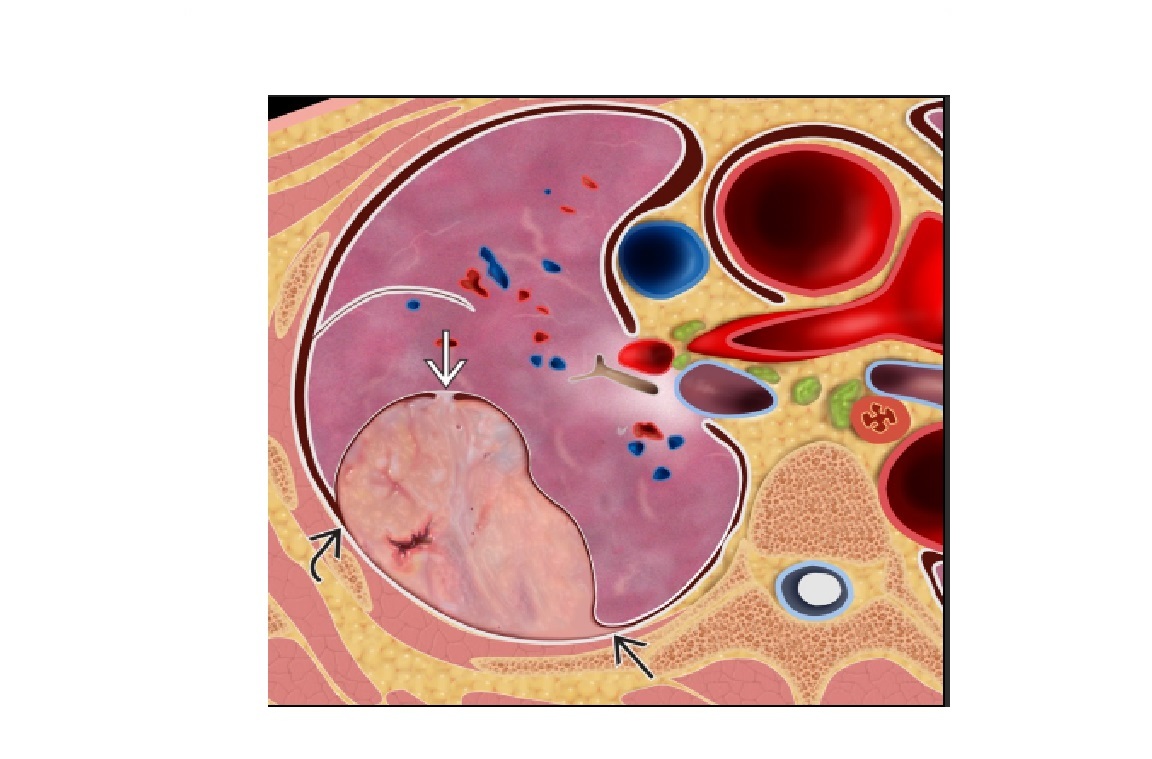

Aspergilloma

Nodule or mass within preexisting cavity

Lies dependent/ Intracavitary movement

Monod sign - gas that surrounds a mycetoma/aspergilloma in a pre-existing pulmonary cavity